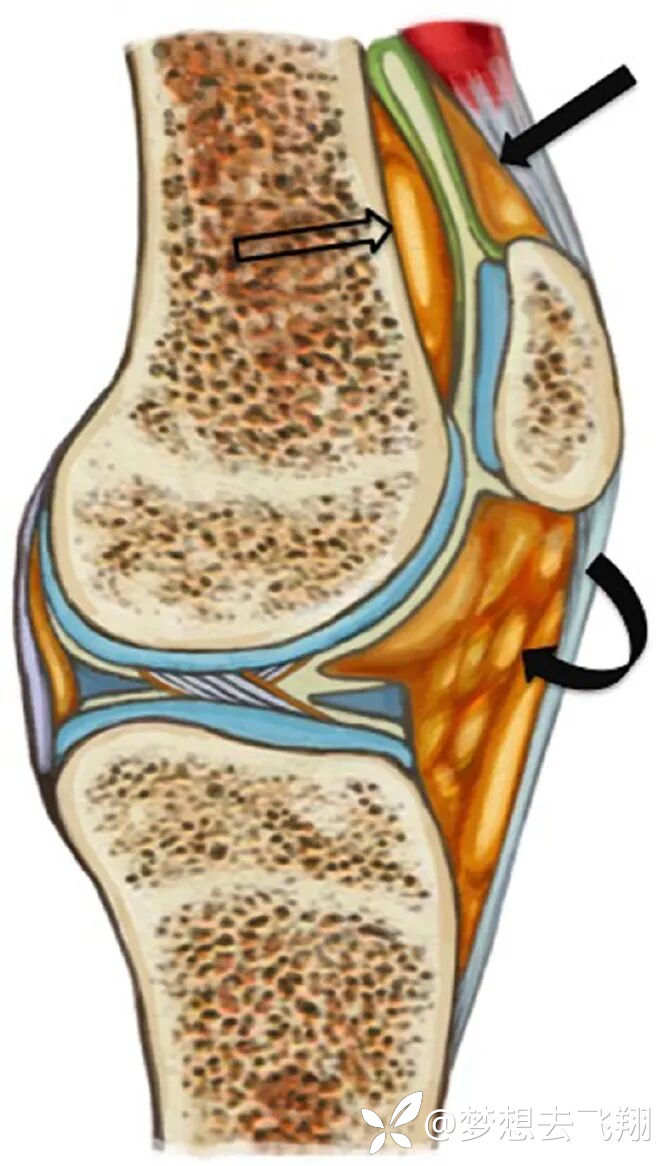

髌骨周围脂肪垫包括髌上脂肪垫、股前脂肪垫和髌下脂肪垫(Hoffa fat pad)(图 4)。

图4:髌骨周围脂肪垫的解剖结构。参考2

图4的解读:髌上脂肪垫(实心直箭头)呈三角形,位于髌骨上方、股四头肌腱后方和髌上凹陷前方。股前脂肪垫(空箭头)位于股骨远端干的前方和髌上凹陷的后方。髌下脂肪垫(Hoffa fat pad)(弯曲箭头)位于髌骨下方,髌腱后方,髁间切迹前方。

膝关节正常屈伸时,髌上脂肪垫防止股四头肌肌腱与股骨髁摩擦,股前脂肪垫防止髌骨与股骨远端干直接接触,Hoffa脂肪垫插入滑车关节面与胫骨上后部和髌韧带前部之间(图5).